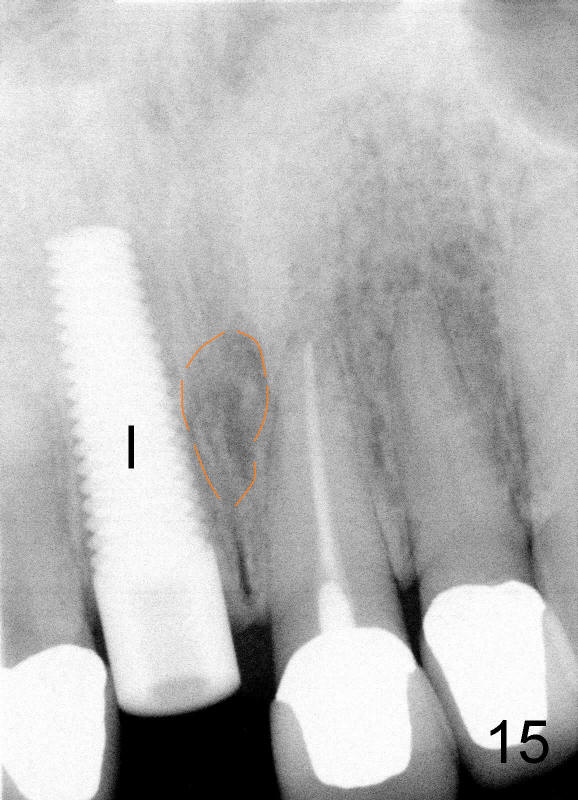

当我们拔出3.5毫米钻头(图五:最后一个钻头)时,就可以看见在舌侧骨板植牙洞型制备(图十一:圆圈)。图十二,图十三分别显示立刻植牙正面观和切缘观,植牙几乎占据所有牙槽窝空间,不需植骨或者缝线。植牙好像没有侵犯邻牙牙根(图十四,图十五,包括七号牙:侧切牙),其实只要熟悉局部解剖(图六至图十),即刻植牙反而容易进行。图十五虚线代表切牙孔,挺接近植牙(I),术后渗血较多,可能与此有关。除此之外,术后病人恢复很快。